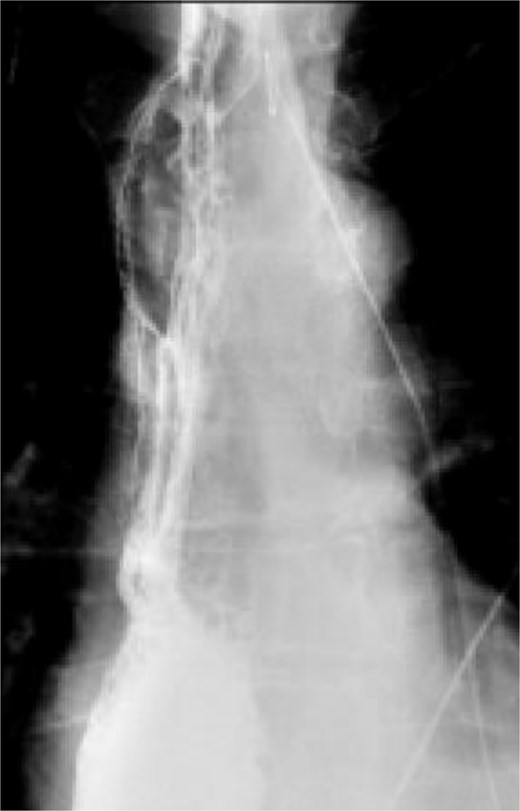

A 58-year-old male with a history of hypertension, daily alcohol use, and 35 pack year smoking history presented with progressive dysphagia and significant weight loss over a period of 3 months. His symptoms began with heartburn, with initial failure of empiric treatment for reflux. He then developed dysphagia to solids that progressed to liquids and eventually an inability to tolerate his own saliva. Over that timeframe, he also noted unintentional weight loss of ~30 lbs. He eventually presented to the emergency department where a CT scan raised concern for an obstructing esophageal mass (Fig. 1). He urgently underwent upper endoscopy revealing a large polypoid tumor with a broad base located in the lower esophagus (Fig. 2). Biopsies revealed a high-grade malignant neoplasm with spindle cell features concerning for a sarcoma. Further workup with brain MRI and positron emission tomography (PET) scan confirmed a hypermetabolic esophageal mass without evidence of distant metastatic disease (Fig. 3). Unfortunately, endoscopic ultrasound was unable to be performed given the nearly obstructive nature of the tumor.

Coronal (a) and sagittal (b) views of the initial CT scan at time of presentation that revealed a large esophageal mass with concern for complete obstruction (arrows).